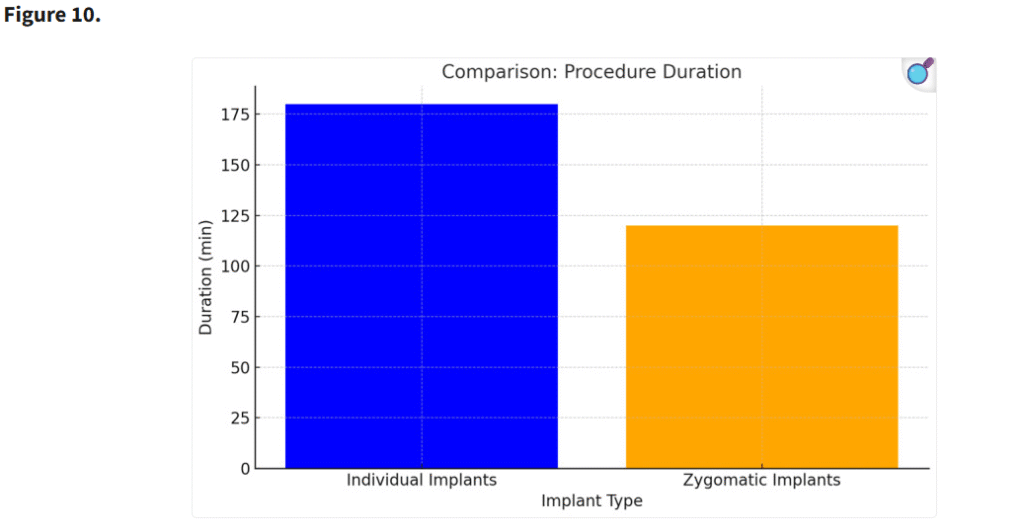

3.2. 手術時間

ザイゴマインプラントの埋入はより短時間で行うことができたが、個別設計インプラントの精緻な埋入は高い精度と安定性を確保し、手術時間がやや長くなる一方で長期的な合併症を減少させる結果となった。ザイゴマインプラントはテンプレートを用いずフリーハンドで埋入されたのに対し、一部の個別インプラントはテンプレートを用いてガイド下に埋入された。個別インプラントにおいて手術時間が長くなったのは、骨をテンプレートに適合させるための調整が必要であったためである。さらに、骨膜下インプラントでは下顎外斜線(linea obliqua)からの骨移植が併用された症例もあり、これによっても手術時間が延長した(Figure 10)。

個別インプラントの手術時間が長くなったのは、骨をテンプレートに適合させるための調整が必要だったためである。さらに、骨膜下インプラントでは、斜線からの骨移植が行われ、手術時間はさらに延長された(p < 0.05)。